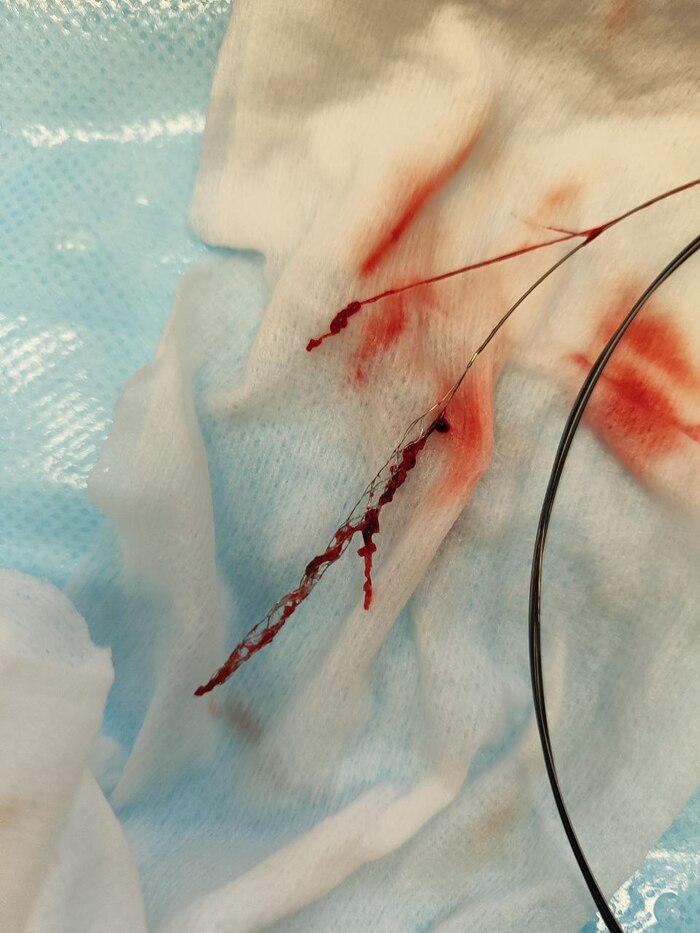

После выполнения стандартных обследований было выполнено КТ г/м - без патологии. Вроде всё складывалось в пользу: "Острой компрессионно-ишемической невропатии лучевого нерва справа", но всё решила проба Данько (это тест для дифференциальной диагностики невропатии лучевого нерва и ишемического инсульта).Пациенту предлагается взять в кисть предмет при невропатии лучевого нерва кисть остаётся в "свислом" положении вместе с предметом рис.1; при ишемическом инсульте при сжатии предмета в кисти она разгибается - рис.2.